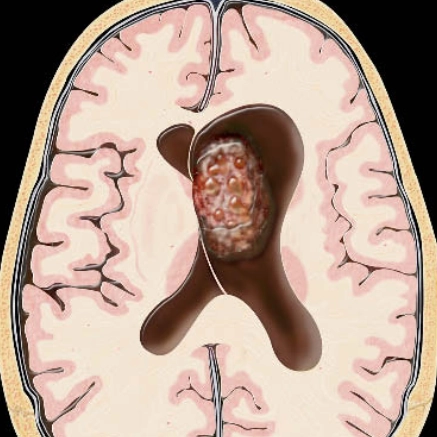

U nguyên bào thần kinh đệm (Glioblastoma- GBM)